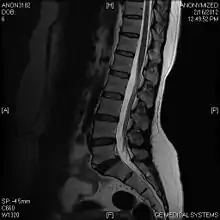

A limbus vertebra is a bone tubercle formed by bone trauma on a vertebral body, bearing a radiographic similarity to a vertebral fracture. The anterior-superior corner of a single vertebra is the common site for this defect although it can also be seen at the inferior corner as well as the posterior or anterior margin. Anatomically, it is assumed to be an intra-vertebral body herniation of the disc material occurring during adolescent growth spurt when the ring apophysis has not yet fused. It was first described by Schmorl in 1927[1] and later in detail by Leif Sward and Adad Baranto.

Viewed in a lateral radiograph, it appears as a triangular shaped bone fragment, not unlike an anterior lip fracture, but with softer edges.

Limbus vertebra is not always symptomatic, but severe cases may lead to more serious pathological conditions and chronic pain. In rare instances, a posterior limbus vertebra has been described causing radiculopathy due to nerve root compression. [2]